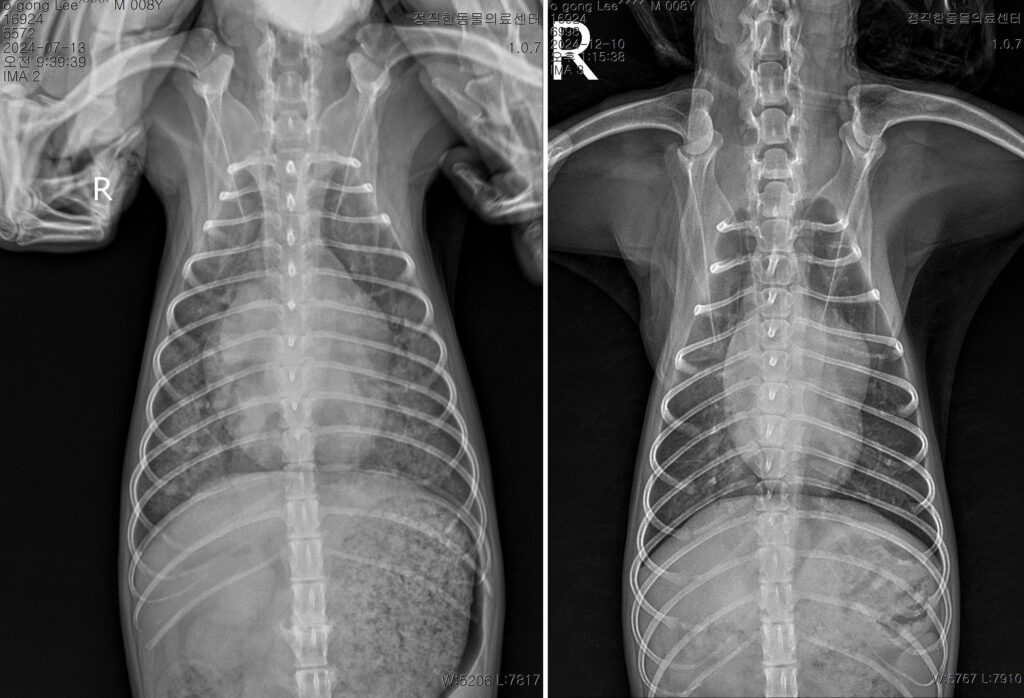

호흡기 내과

기침, 호흡 곤란, 숨소리 변화는 생명을 위협할 수 있는 중요한 증상입니다. 기도, 폐, 흉강 질환을 면밀히 평가해 호흡 상태에 맞춘 치료와 관리 계획을 세웁니다.

순환기 내과

심장은 전신 건강의 중심입니다.

심장 질환의 진행 단계와 아이의 상태를 고려해 약물 조절과 장기적인 심장 관리 치료를 시행합니다.